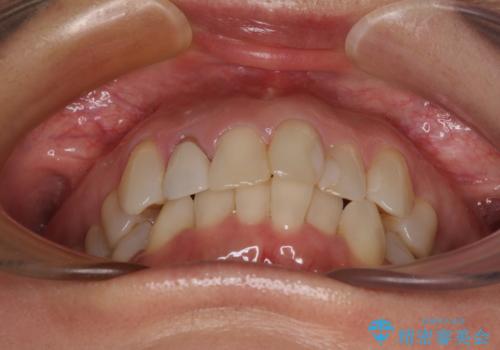

前歯のデコボコとむし歯治療の跡 インビザライン矯正とオールセラミッククラウン治療

- 前歯のセラミッククラウンの縁が見えることが気になってから、デコボコも気になるようになってきたとのことで来院された患者様です。

デコボコの程度は中等度であったため、インビザライン・モデレートパッケージにて歯列を整えることとしました。

セラミッククラウンの装着されていた前歯と、大きな修復治療の跡がある反対側の歯は、矯正治療後に補綴治療を行うこととしました。